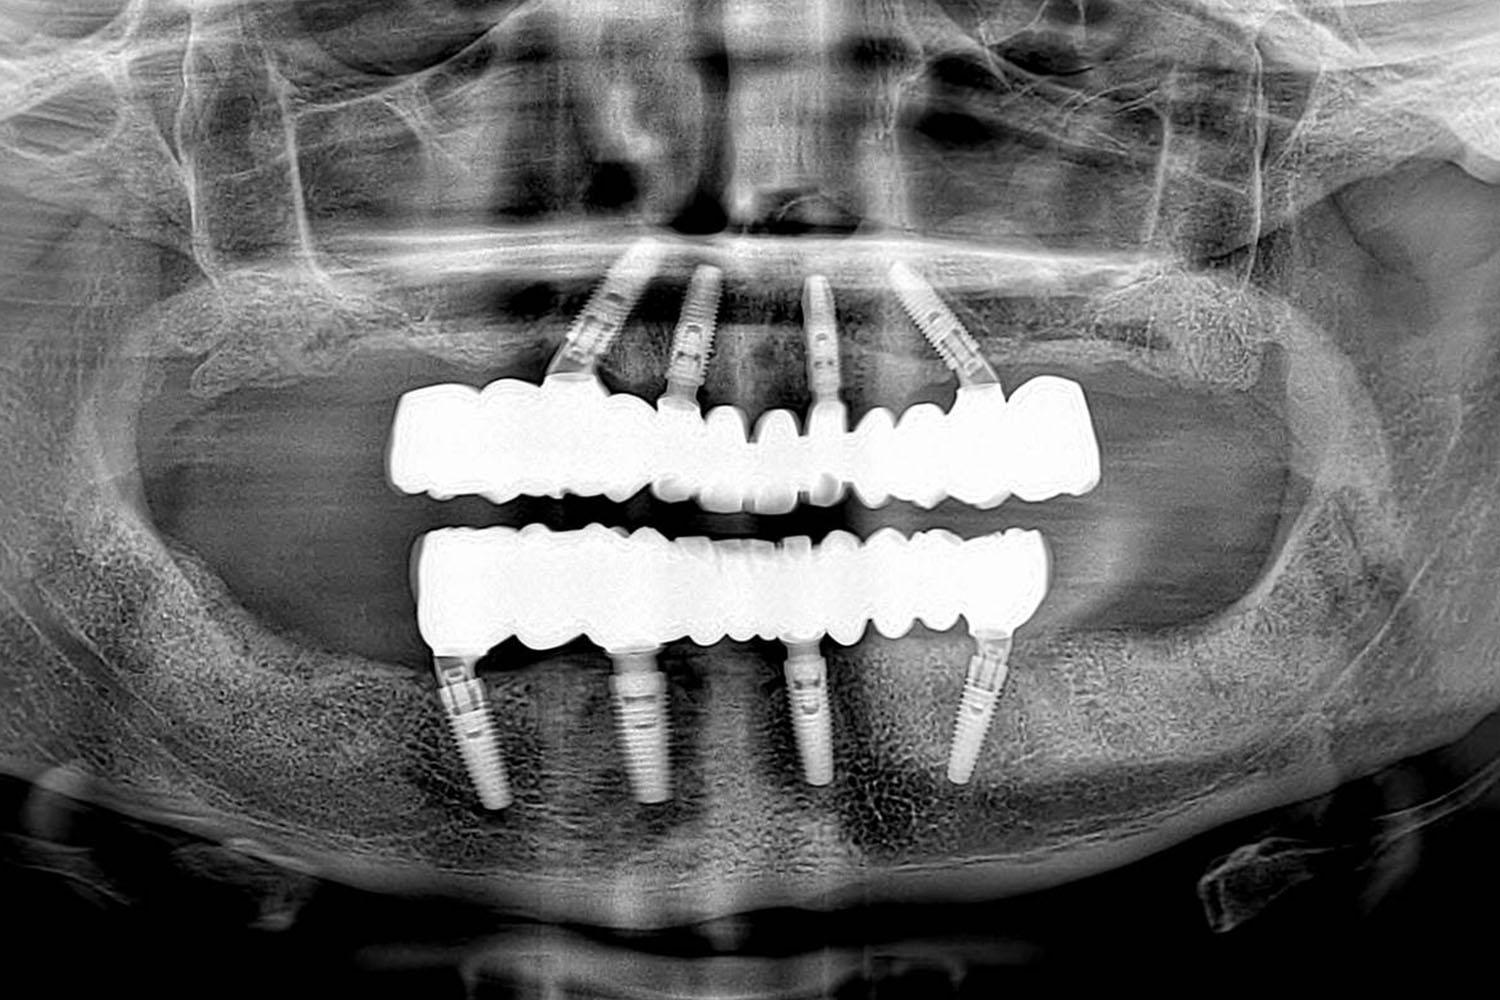

Terapija se temelji na ugradnji četiri implantata u čeljust koji služe kao stabilna sidrišta za fiksni zubni most.

U mnogim slučajevima pacijent dobiva privremene fiksne zube već isti dan.

Prikaz stvarnih rezultata postignutih All-on-4® terapijom kod naših pacijenata.